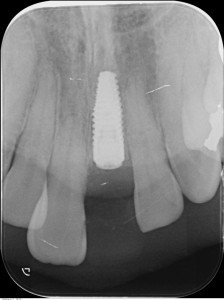

使用したインプラントはストローマンBLT4.1Φ12mmで、しっかりと固定できました。

インプラント埋入後のレントゲンです。